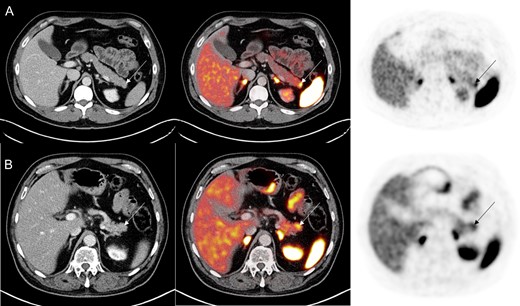

A 48-year-old Caucasian male with a medical history significant for hypertension was referred to the general surgery clinic for chronic abdominal pain for the past 6 months. The patient was suffering from nausea, postprandial facial flushing and crampy/colicky epigastric pain radiating to the RLQ. Initial laboratory work up including complete blood count, complete metabolic panel, serum CA-19-9, serum CEA, urinary 5-HIAA, serum chromogranin A and serum neuron specific enolase were all unremarkable. Additionally, right upper quadrant ultrasound and CT abdomen/pelvis were unremarkable. However, the patient symptoms persisted, and therefore a 68Ga DOTATATE PET/CT scan was ordered. Imaging revealed increased DOTATATE activity (SUV 9.7) in the distal pancreatic tail without an underling mass on CT (Fig. 1A). EUS fine needle aspiration was unremarkable. Additional laboratory analysis revealed elevated C-peptide (4.9 ng/ml) and proinsulin levels (76 pmol/l), concerning for an insulinoma. In addition, a HIDA scan showed a gallbladder ejection fraction of 34%, consistent with chronic cholecystitis.

(A) 68Ga PET/CT DOTATATE demonstrating increased DOTATATE uptake (SUVmax 9.7) in the distal pancreas without underlying pancreatic mass in the first case study. (B) In the second case study, 68Ga PET/CT DOTATATE revealed increased DOTATATE uptake (SUVmax 7.6) in the pancreatic tail without any CT abnormality.

A 68-year-old male with a medical history for hypertension and type 2 diabetes mellitus, was referred to the general surgery clinic with three bouts of acute pancreatitis of unclear etiology from February 2017 to March 2018. He had intermittent severe postprandial epigastric pain and nausea. Patient denied other symptoms. Initial laboratory work up was unremarkable except for an elevated chromogranin A (393 ng/ml). CT abdomen and pelvis as well as magnetic resonance cholangiopancreatography were unable to identify any lesion. Therefore, the patient underwent a 68Ga DOTATATE PET/CT scan which revealed increased uptake in the distal pancreas (SUVmax 7.6) without any underling lesion (Fig. 1B). EUS fine needle aspiration showed no abnormalities. Given the multiple bouts of acute pancreatitis, he was recommended to have a laparoscopic distal pancreatectomy and splenectomy. Intraoperative ultrasound demonstrated a normal pancreas. Pathology revealed a NET (10 mm in size) and margins were negatives. Eleven benign lymph nodes were resected. His 2-week postoperative follow up in late April 2018 was unremarkable. He denied new symptoms and previous symptoms have resolved. No imaging or laboratory work up was done at this time.

Although these markers are highly sensitive and specific for NETs [9], there was no morphological evidence of any lesion. However, both did have functional evidence of NET on the distal pancreas (Fig. 1). EUS studies were unremarkable and unable to give a tissue diagnosis, which may have been secondary to the presence of pancreatitis or the location of the lesions in the distal pancreas. The patients underwent laparoscopic distal pancreatectomy and splenectomy and there was microscopic evidence for NET in the pathologic specimens.